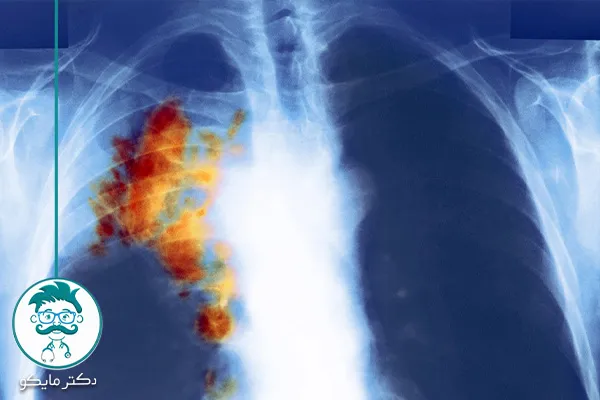

عکس سرطان ریه بدخیم

تودههای بدخیم در ریه در تصاویر پزشکی معمولاً به صورت تودههای نامنظم و غیرقابل کنترل دیده میشوند که به تدریج به سایر قسمتهای بدن انتشار مییابند.

- پت اسکن (PET scan): برای شناسایی فعالیت متابولیک غیرعادی.